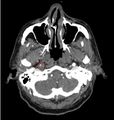

- Infarct on Head CT

- Basilar Skull Fracture